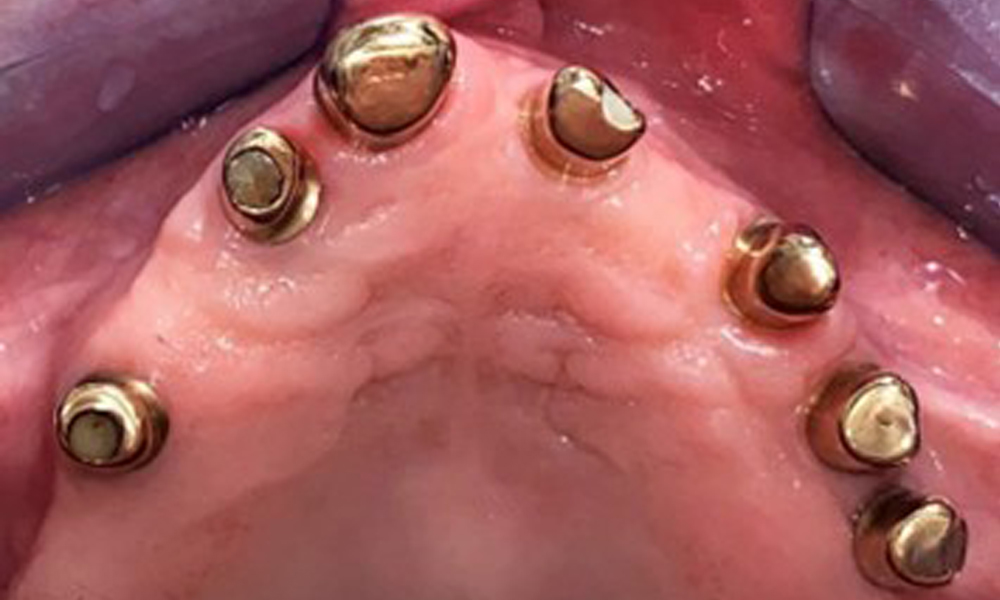

The patient was fitted with a combined removable maxillary telescopic prosthesis more than 25 years ago (Fig. 1, Fig. 2, Fig. 3) and is very happy with her dentures. The patient has an adequate fixed denture for the mandible (Fig. 4).

The dental findings are as follows: Combined removable implant and tooth-supported telescopic prostheses on implants 15, 13, 21, 23, 24, 25 and tooth 11 (Fig. 1, Fig. 2, Fig. 3). The patient was fitted with a fixed mandibular denture. Adequate bridges were present over 37 to 34 and 45 to 47 (Fig. 4), the crown margins were intact and there were no active caries. A composite filling with a marginal gap was present on tooth 43. There was mandibular gingival recession, exposing 1 to 3 mm of root surface. This also applies to 11.

Occlusal view: Maxilla with removable, palateless denture.

Fig. 3: Occlusal view: Maxilla with removable, palateless denture.